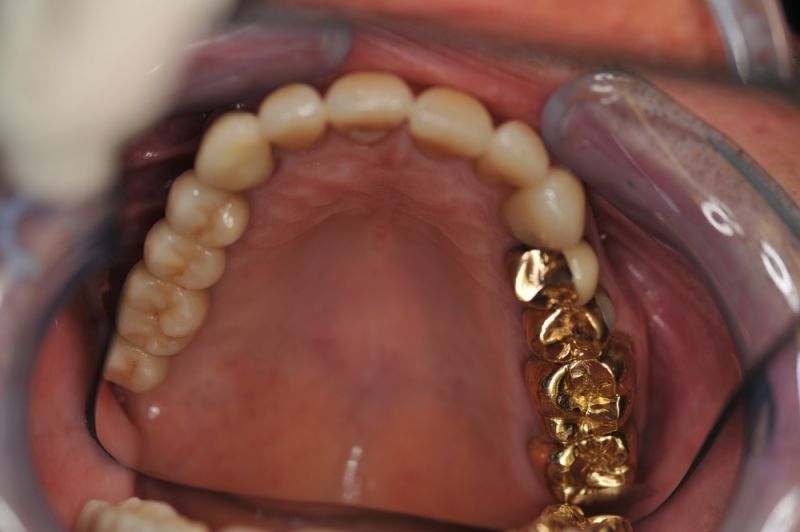

Rekonstruierter Kieler Patient im Recall

Die funktionstherapeutische Rekonstruktion befindet sich seit 17 Jahren im Munde des Patienten.

Gemeinsam ist man der Auffassung, dass sich heute zum Glück auszahlt, dass man beizeiten die Fundamente im Mund geschaffen hat, von denen der Patient heute im Alter zehrt.